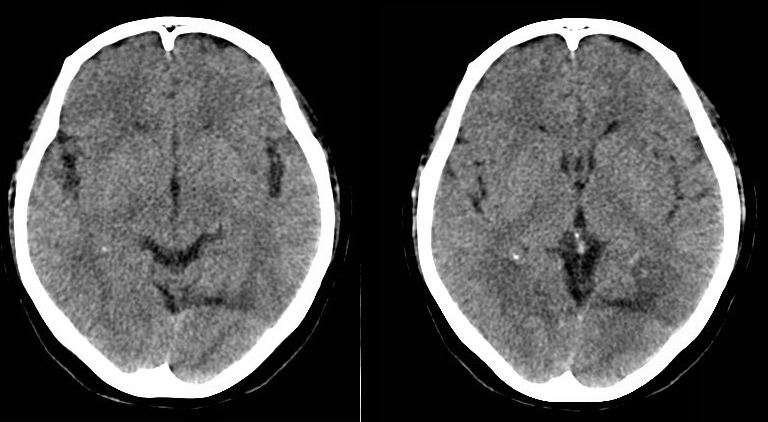

病人资料:女,57岁,反复头痛6年余,无恶心、呕吐等症状,体查:bp180/100mmhg。

中线脂肪瘤

胼胝体发育不良并脂肪瘤形成,脂肪瘤形成是因,胼胝体发育不良是果。如果正规些应该是中线脂肪瘤并胼胝体发育不良!

典型中线脂肪瘤

胼胝体发育不良

中线脂肪瘤并胼胝体发育不良。

形态 范围都像伪影